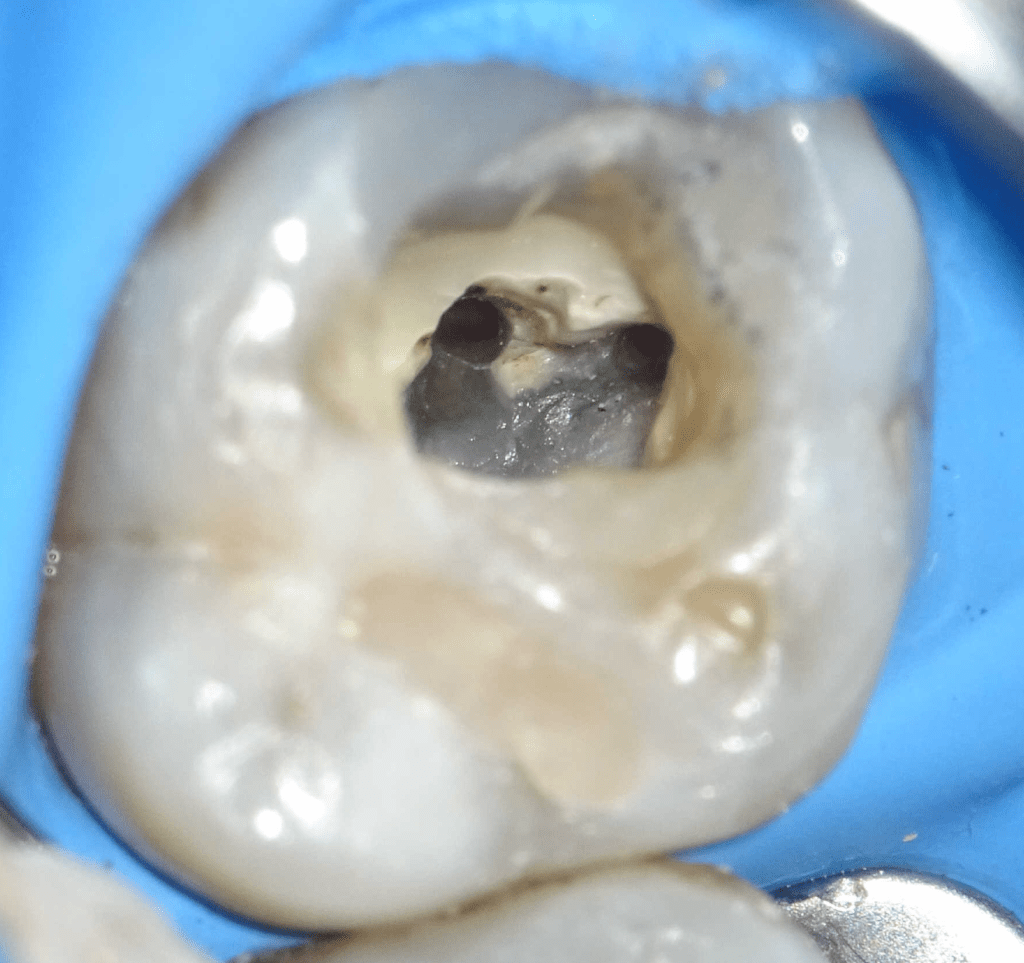

Reco preendo + 4 conductos molar superior